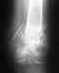

Прошу прощения не совсем понял как крепить снимки, ссылки:

http://s02.radikal.ru/i175/1011/92/3000d43b9083.jpg - 15.10.09

http://i080.radikal.ru/1011/da/005b85bb2bc0.jpg - 03.07.10 спустя 9 мес.

http://s016.radikal.ru/i337/1011/77/6521a8b92daf.jpg - 17.11.10 спустя год и один мес.